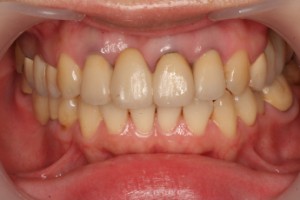

初診時の写真です。左の前歯が喪失して歯肉もへこみ歯も大きいな形となっていました。